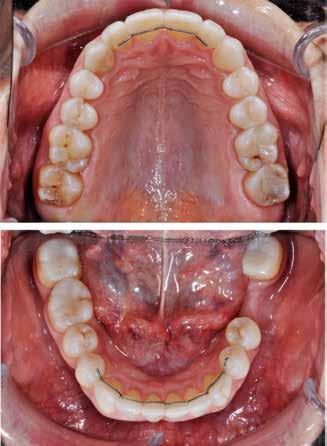

Der planlægges alignerbehandling af begge kæber med intrusion af 1+1 og 2,1-1,2, nivellering af trangstilling UK med interproksimal reduktion (IPR) (Fig. 2 A, B) og senere IPR OK for reduktion af dark triangles mellem incisiverne efter nivellering. Patienten instrueres i at benytte alignere 20-22 timer/ dag med alignerskift hver 7. dag, og patienten ses hver 3.-8. uge under forløbet. Den første alignerserie består af 16 alignere for nivellering OK/UK og IPR i UK (Fig. 2). Efter denne serie planlægges IPR mellem incisiverne i OK for reduktion af dark triangles (Fig. 3) samt yderligere intrusion af OK og UK-fronten i 12 refinement-alignere. Patienten udviser god kooperation og er meget tilfreds med alignerapparaturet, som er mindre synligt end det faste apparatur (Fig. 4).

Behandlingen afsluttes med yderligere refinement-alignere for finindstilling af okklusionen, og efter 11 måneders ortodontisk behandling er der opnået normale relationer i alle tre